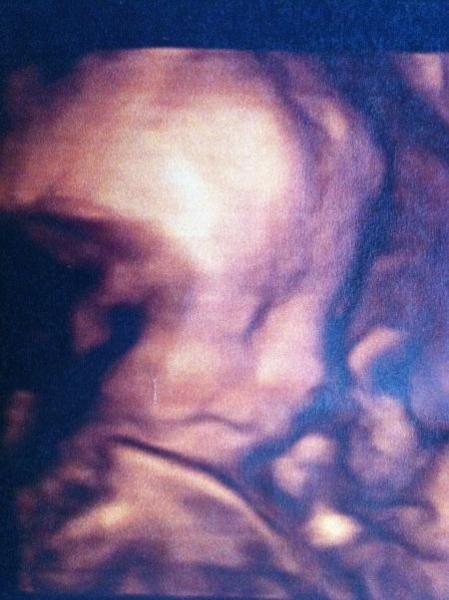

Hallo Mädels, ich bin jeden Tag bei euch nur fehlt mir grad im Alltagswahnsinn die Zeit zum schreiben. Aber heute hatte ich ein soo tolles Erlebnis. Letzte Woche bei der Vorsorge sagte mein FA das die Masse der Oberschenkel und des Kopfes passen würden aber die des Bäuchleins um 3 WOchen zurück lägen. Daraufhin bin ich heute auf eigene Faust zu meinem Prenataldignostiker der auch der Meinung das sie hinterher hinkt aber er meinte nur 1-1,5 Wochen und das sie eben kein Riese wird. Was nach wie vor ist das ich in der linken uterina einen leichten WIderstand habe der das Wachstum beeinflussen kann. Daraufhin bin ich zu meinem Gyn und habe ihn gebeten doch jetzt von 4 Wochen Abständen auf 2 Wochen Abstände zu gehen einfach weil ich Angst habe und er stimmte zu. Was aber ganz toll war heute ist , ich hatte ja diese Bauchdeckenstraffung und noch nie , bei keinem meiner 8 Kids habe ich ein 3 D Bild bekommen . Erst gab es das nicht und dann hatte ich die Narben. Heute hat bevor der Doc kam erst die Schwester vermessen und auf einmal schaltet die auf 3 D. Ich war zu Tränen gerührt. Und dann kam nochmal ein ganz anderes Bild wo sie mir erklärte das das der allerneuste 3 D wäre den sie noch nicht probiert hätte und ich wäre ihr Versuchtsobjekt. Wahnsinnsfotos.......... ich könnte die kleine Maus jetzt schon knutschen Ich hänge sie euch mal an....so ein tolles Erlebnis....für mich...denn Mausi hatte einmal einen Arm, dann den Zweiten Arm und dann beide Arme vorm Gesicht. Dann hat sie den Bauch eingezogen beim Messen (typisch Weib) und dann hat sie uns die Zunge rausgestreckt aber das wollte sie net als Photo drucken weil sie meinte da bekämen die Geschwister ja Angst. Sorry jetzt isses so lang, aber dafür schreib ich ja nicht so oft :-) Ich wünsch euch allen einen tollen Abend Drücklerle Nicole mit den 8 Kids und Laylani inside

Was für geniale Bilder! Da sieht man ja kaum noch, dass es noch im Bauch ist. ;)